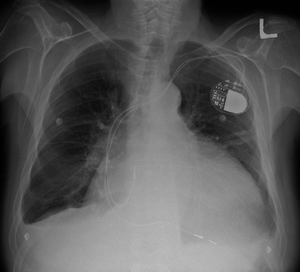

Cardiomegally.PNG

Cardiomegaly on chest X-ray with a pacemaker

Medical devices to regulate the heartbeat

• Pacemaker: Coordinates the contractions between the left and right ventricle. In people who may be at risk of serious arrhythmias, drug therapy or an implantable cardioverter-defibrillator (ICD) may be used.